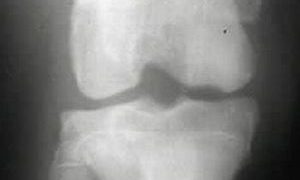

骨軟骨症(osteochondrosis) ~ 離断性骨軟骨症(炎) ~ 脛骨粗面骨軟骨症(炎)

生後一定期間の間、骨端および骨端軟骨を中心に骨は成長します。椎骨においても、ほぼ同様の成長がみられます。この成長の時期に、骨端部周辺に壊死を生じ崩壊し、その後修復が行われ、帯痛性の跛行を現す一群の疾患を骨軟骨症(または骨軟骨炎osteoch...